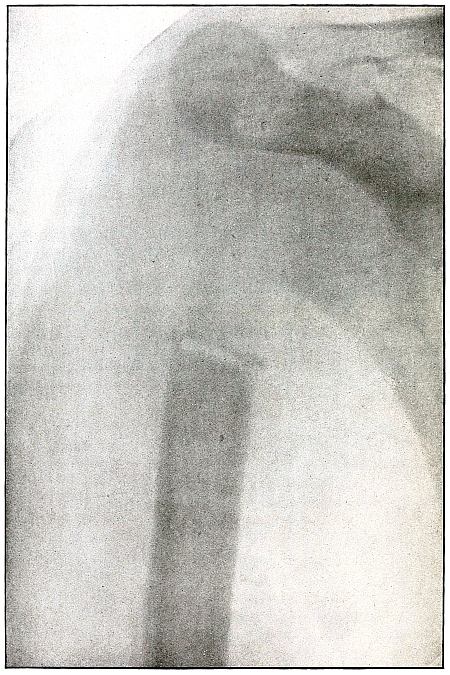

Gunshot wound, shoulder |

174 |

| 83. |

Gunshot wound, shoulder |

176 |

| 84. |

Gunshot wound, shoulder |

178 |

| 85. |

Gunshot wound, shoulder |